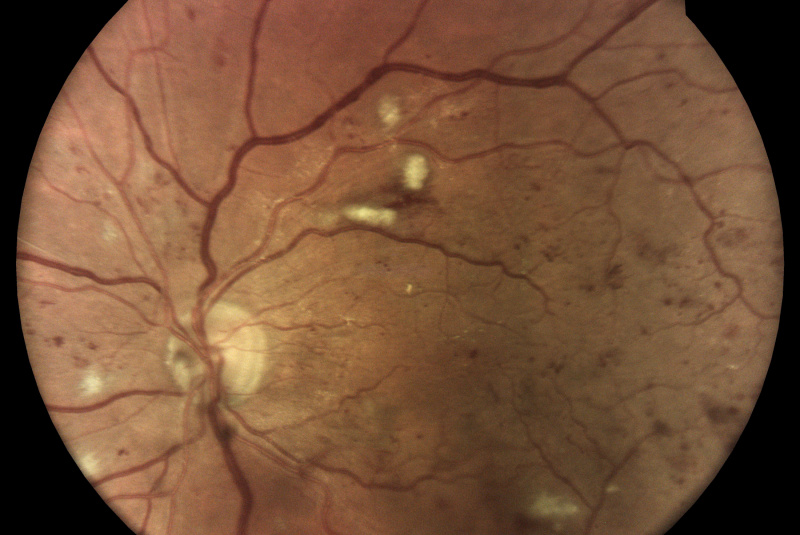

Oproti běžným fundus kamerám je zde využita patentovaná technologie iCare DRS Plus Confocal Technology. Snížená intenzita záblesku má šetrnější účinek na zornici. Prostřednictvím tohoto nemydriatického zařízení je možnost vidět jemné struktury sítnice a cévního systému i skrze velikost zorničky od 2,5 mm.

Fundus kamera iCare DRSplus pořídí celkem 4 vysoce kvalitní snímky (dva z pravého a dva z levého oka), které se automaticky ukládají na cloud a posílají se na zpracování AI - umělé inteligenci. Report je dostupný ihned a ten je možno konzultovat s pacientem během téže návštěvy u lékaře.

- infračervené mapy zvýrazňující světlé a červené léze/poškození